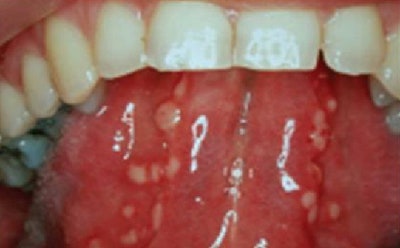

설백태